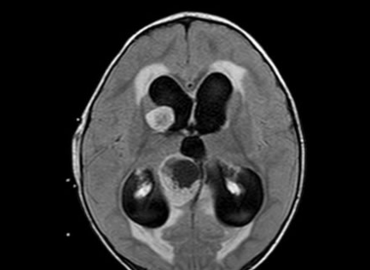

Paciente masculino de 11 años de edad. MC: dolor y debilidad de MMII izquierdo, asociado a cefaleas esporádicas de 3 […]